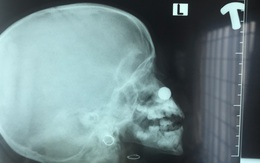

Nhét pin vào mũi, bé gái 4 tuổi bị axit phá hủy niêm mạc

TTO - Ngày 19-2, bác sĩ Hồ Lê Hoài Nhân - phó giám đốc Bệnh viện Tai mũi họng Cần Thơ - cho biết bệnh viện vừa tiếp nhận cấp cứu bé 4 tuổi do nhét pin đồ chơi vào mũi, niêm mạc bị phá hủy.